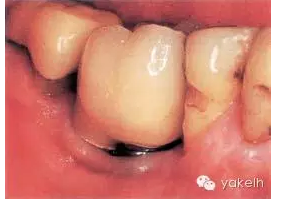

LR6由2顆種植體修復(fù)。2顆種植體之間距離過近(圖.1)。通常情況下,單個(gè)磨牙缺失僅需植入單個(gè)直徑較寬的種植體即可。影像學(xué)顯示這2顆種植體周圍有大量的骨喪失(種植體周圍炎表現(xiàn))(圖2)。

圖.1 下頜磨牙由2顆位置不恰當(dāng)?shù)姆N植體聯(lián)合修復(fù)